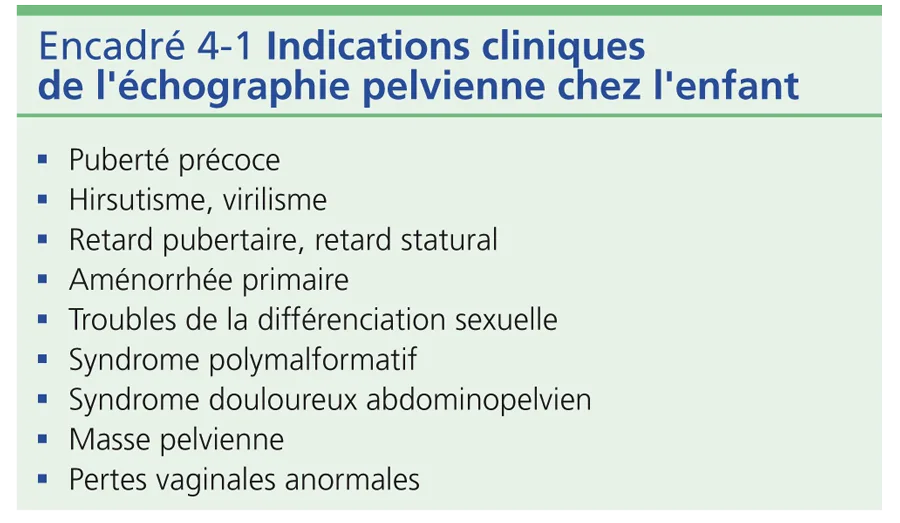

L’utérus des nouveau-nés paraît volumineux du fait de la petite taille du pelvis et de son développement transitoire dû à l’imprégnation normale maternelle pendant la grossesse. Il est épais avec un corps aussi épais que le col, mesuré de 1 à 1,5 cm (fig. 4-1). Sa hauteur est de 3,5 à 4,5 cm. La cavité utérine est soulignée par un écho dense médian, témoin d’un léger développement de l’endomètre. Le vagin sous-jacent présente des parois musculaires hypoéchogènes épaisses, bien visibles. Cet aspect de gros utérus à la période néonatale disparaît en quelques semaines ou mois pour adopter la morphologie impubère normale [1–3]. L’utérus impubère a une morphologie particulière « en goutte » avec un corps utérin fin par rapport au col et à l’isthme plus épais, formant les deux tiers du volume utérin (fig. 4-2A). Le rapport corps sur col est inférieur à 1. La hauteur utérine est mesurée à 3 cm ± 0,5 cm. La taille et l’aspect de l’utérus restent inchangés jusqu’à l’âge de 8 à 9 ans. Son échostructure est hypoéchogène, homogène. La ligne cavitaire n’est pas visible. Un fin écho cavitaire est parfois vu au niveau du col. Les parois vaginales sont fines.

À la puberté (fig. 4-2B), sous l’influence des œstrogènes, l’utérus grossit progressivement et sa croissance s’effectue au niveau du corps qui s’allonge et s’épaissit. L’utérus devient ainsi tubulé puis prend son aspect piriforme pubère. En fin de puberté, il mesure 6 à 6,5 cm de hauteur. La cavité utérine est visible sur toute la hauteur utérine, ce qui témoigne de l’épaississement des parois musculaires, puis de l’épaississement progressif de l’endomètre.

Les critères échographiques du développement utérin par imprégnation hormonale sont donc : ■ hauteur utérine supérieure à 3,5 cm ; ■ épaississement du corps avec un rapport corps/col supérieur à 1 ; ■ visibilité d’une ligne cavitaire échogène sur toute la hauteur utérine.

Ces modifications utérines pendant l’enfance sont schématisées sur la figure 4-3.